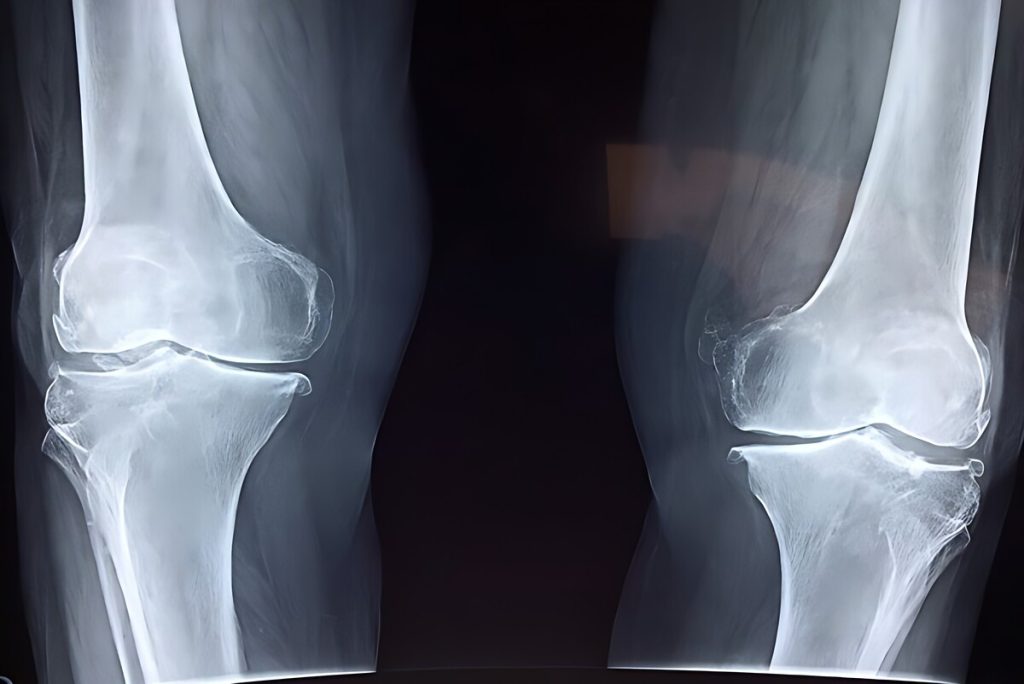

آسیب به استخوانها

نخستین نگرانی، تاثیر منفی بر سلامت استخوانهاست. مصرف نوشابه و الکل هر دو با کاهش تراکم مواد معدنی استخوان و افزایش خطر شکستگی مرتبط است. مصرف نوشابه بهدلیل وجود اسید فسفریک میتواند تعادل کلسیم و فسفر را بر هم بزند و خطر شکستگی لگن را افزایش دهد. مصرف الکل نیز با کمبود کلسیم، اختلالهای کبدی و کاهش ویتامین دی همراه است که همگی به تضعیف استخوانها منجر میشوند.